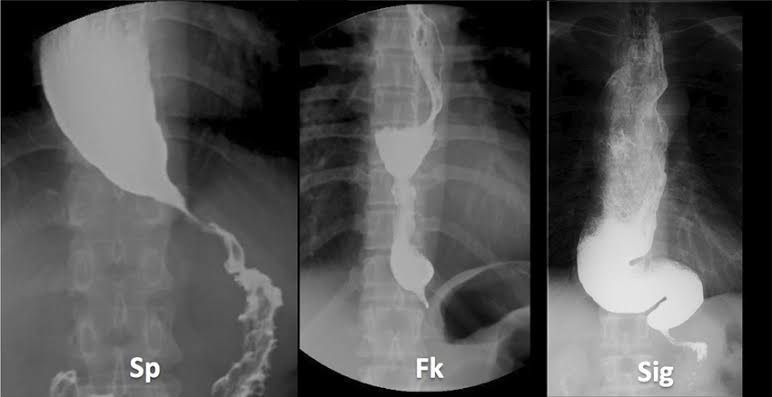

Complications of achalasia treatments include: Creation of a hole in the esophagus. Lack of success and return of achalasia symptoms. Gastroesophageal reflux disease. Bloating.